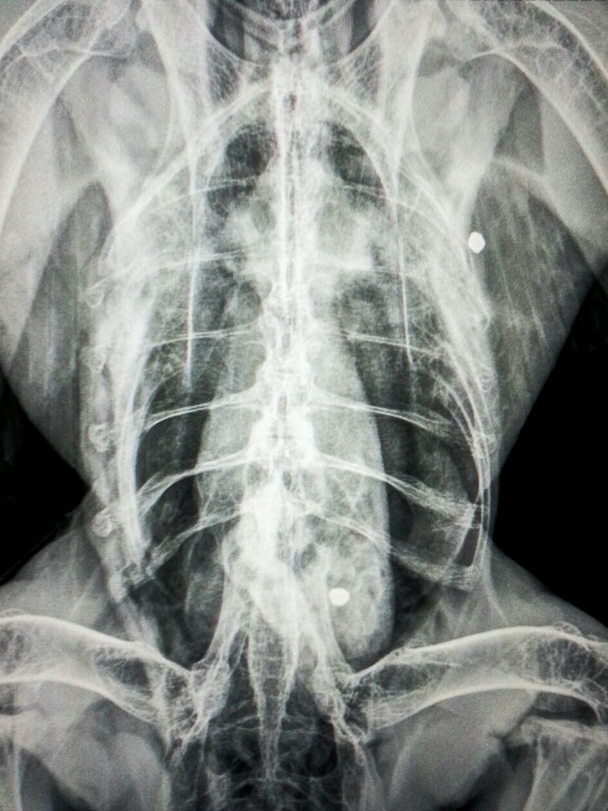

O animal estava bastante prostrado. Recebeu os primeiros socorros e foi colocado em observação para realização dos exames clínicos. Na manhã do dia 09 de abril, após exame físico minucioso, percebeu-se um grande edema na região abdominal, e as radiografias revelaram dois projéteis de chumbo alojados no corpo do animal. A ave foi medicada e colocada em observação novamente. Mesmo com todos os cuidados tomados, ela não resistiu e morreu no início da tarde.

A equipe do laboratório de patologia do hospital realizou a necropsia logo após o óbito, e o laudo conclusivo sobre as causas da morte deve sair em 30 dias. Porém, a equipe adiantou que a harpia apresentava lesões indicativas de trauma, como presença de fraturas em quilha e sinsacro, além de hematomas em abdômen e cabeça e hemorragias em encéfalo e lateral do globo ocular, sendo todas as lesões encontradas no lado direito. Além disso, os projéteis de chumbo foram encontrados um em musculatura peitoral esquerda e outro dentro da cavidade celomática. Aparentemente, não havia correlação das balas com os traumas recentes.